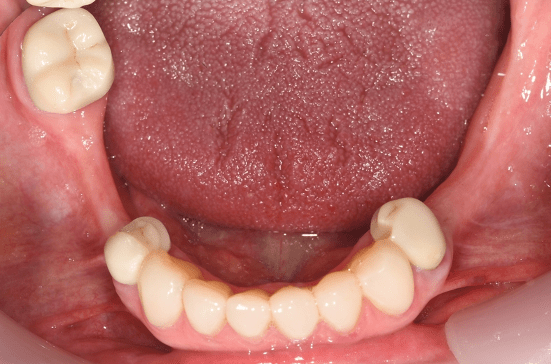

Metal dentures can be provided when there are a number of stable teeth to help support and hold the denture in place. It is often a healthier way to replace the teeth as it can minimise the coverage of the gums and movement that may harm the health of the remaining teeth. Selective crowns may be needed to optimise the support and retention.